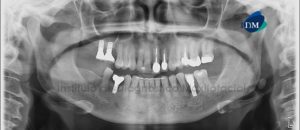

Paciente femenino de 51 años de edad, es referido al Instituto de Diagnóstico Maxilofacial – IDM para evaluación general. En la reformación panorámica de la